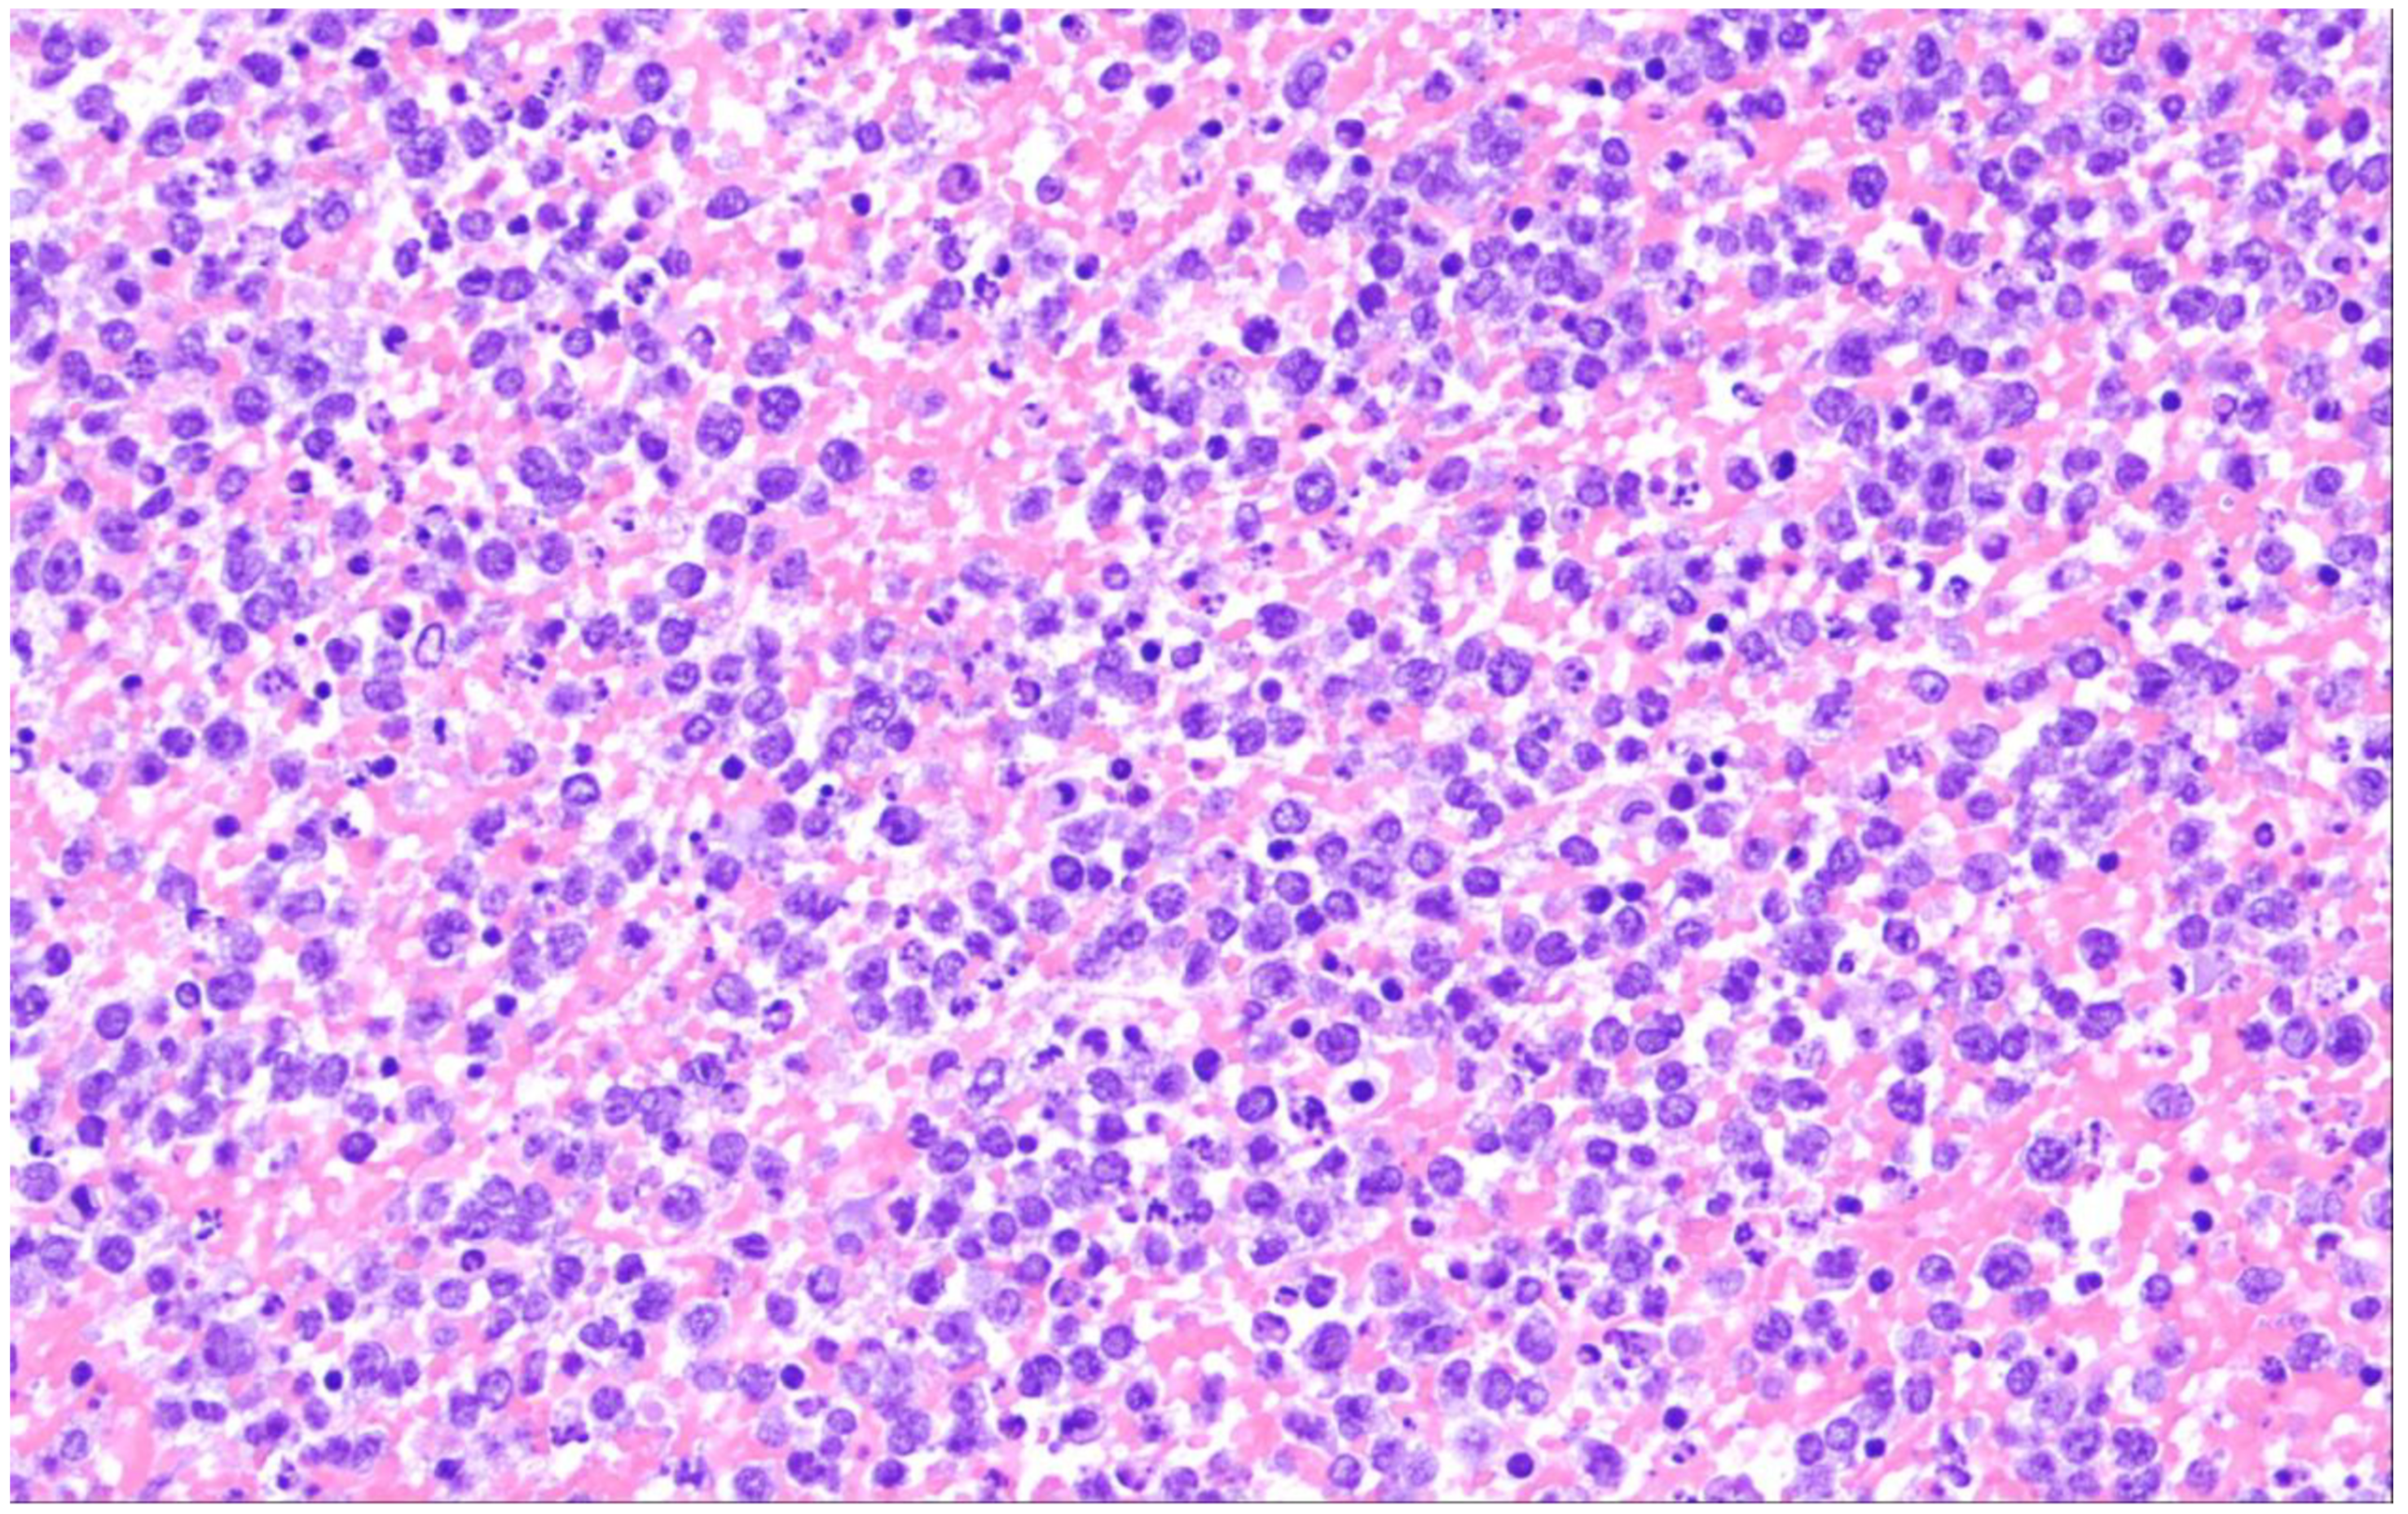

14. Plasmablastic Lymphoma

| Plasmablastic lymphoma |